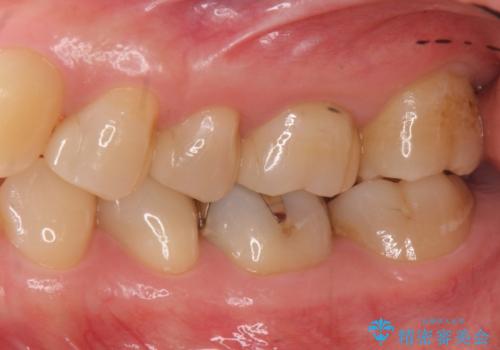

3本仮づめのまま放置 セラミックインレーへ

目立たない白いものがご希望とのことで、セラミックインレーで修復しました。

- 21万円(左上567:セラミックインレー 7万円x3本)費用は治療当時の料金となります

仮づめの状態でしたが、そこまで中は虫歯になっておらず、神経の治療も不要でした。